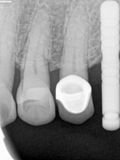

R5.jpg